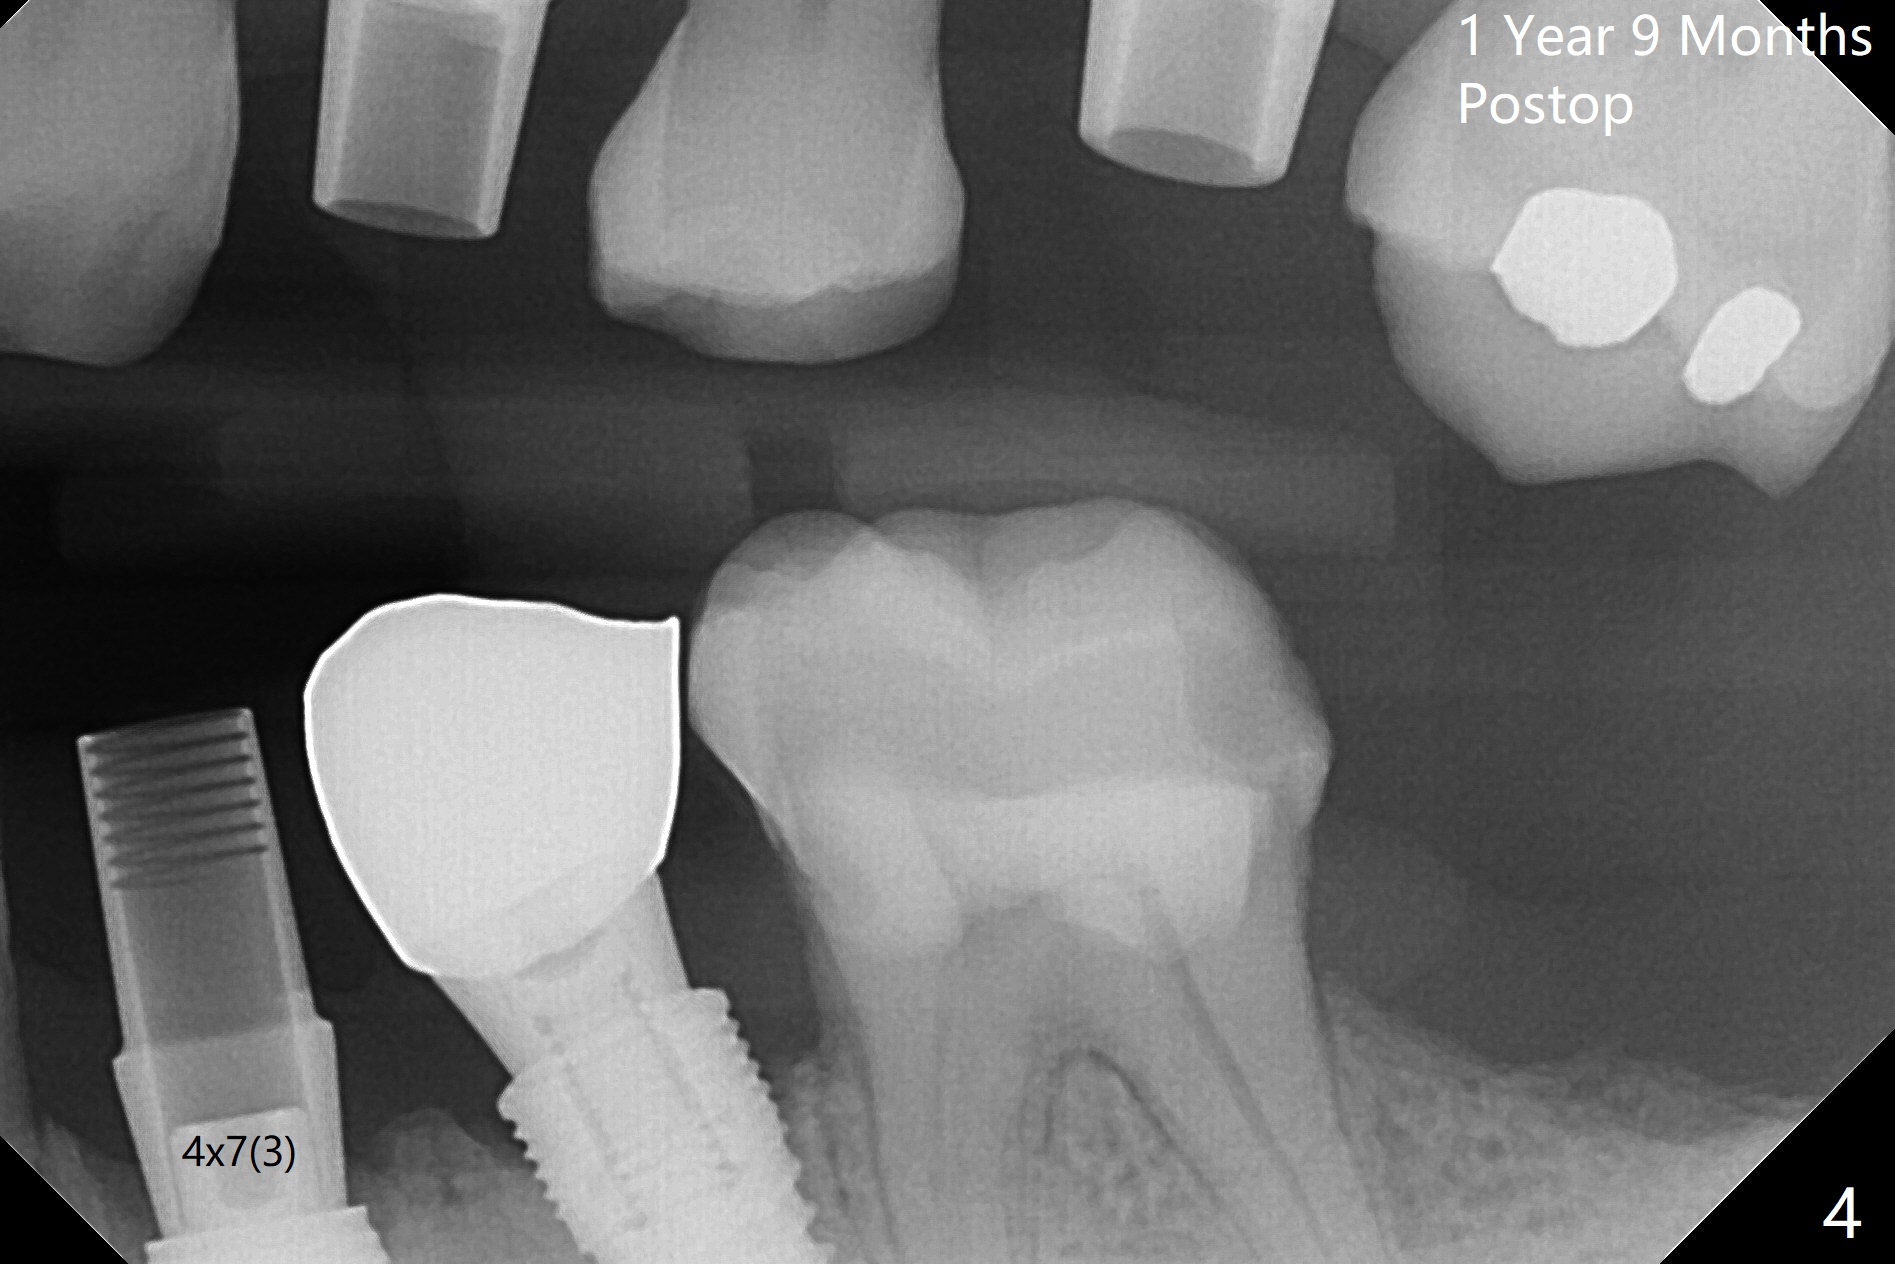

To remove the subgingival residual root of the tooth #12, buccal flap is raised, which provides access to see thread formation in the coronal portion of the socket following use of cortical tap. Bone harvested from osteotomy is placed in the remaining buccal socket (Fig.1). Bone density is so high at #21 that 4.5x8.5 and 4.5x10 mm drills are used before placement of a 4.5x10 mm with 12 mm offset in addition to use of cortical tap and back up of the implant several times (Fig.2).